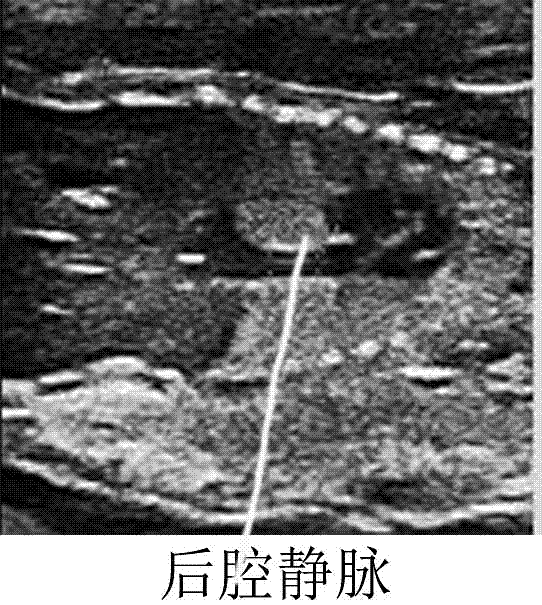

一种预测犬胎龄的方法